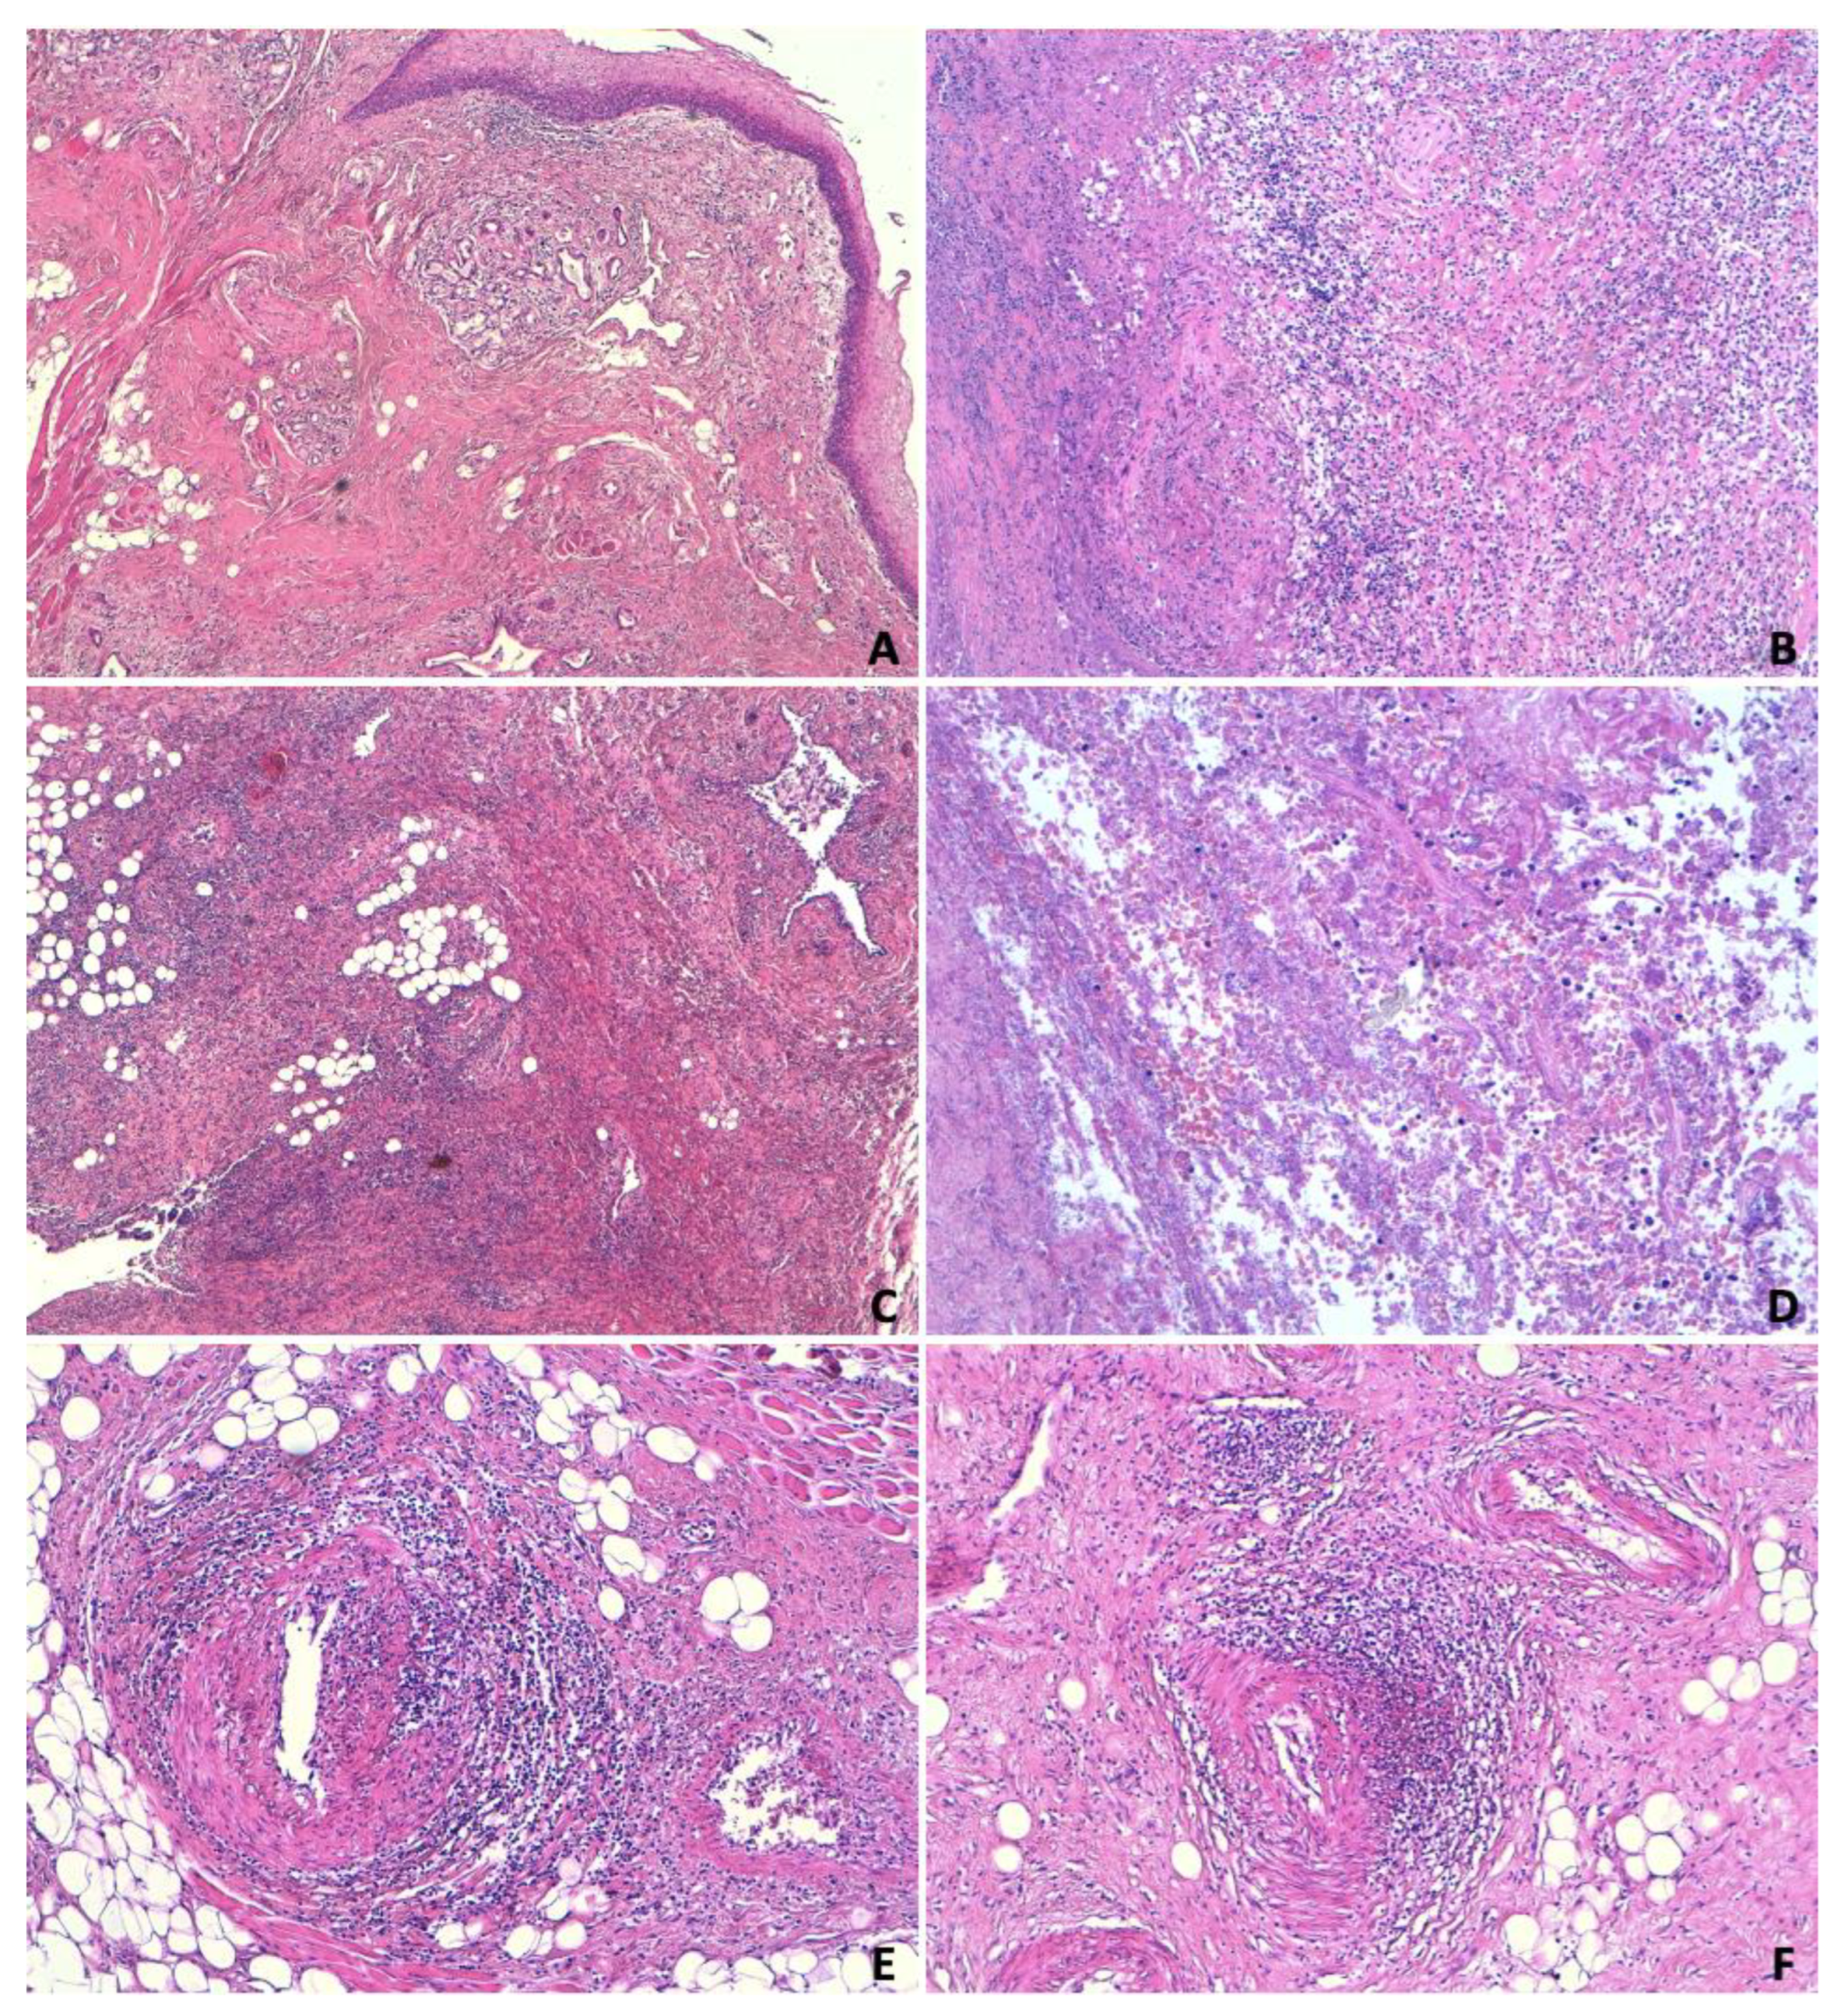

5.2. Histopathological Examination